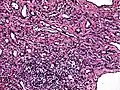

Low power photomicrograph of an endovascular papillary angioendothelioma showing papillae with hyalinized cores

High power view showing a vascular tumor with cuboidal endothelium lining the vessels. Few entrapped seminiferous tubules are also noted (arrow).

Characteristic budding, hobnail-like endothelial cells visible.